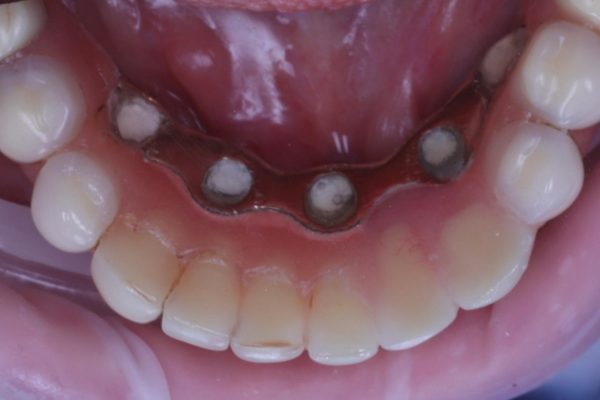

When the implant bridge was off, I was able to irrigate the area and remove the soft plaque deposits present (Figures 5 and 6).

The bridge was replaced, and then the screws torqued down to the manufacturer’s recommendations.

The occlusion and aesthetics were checked, and the patient was delighted that we’d managed to refurbish the bridge and achieved her goals. The final result is shown in Figures 7-11.